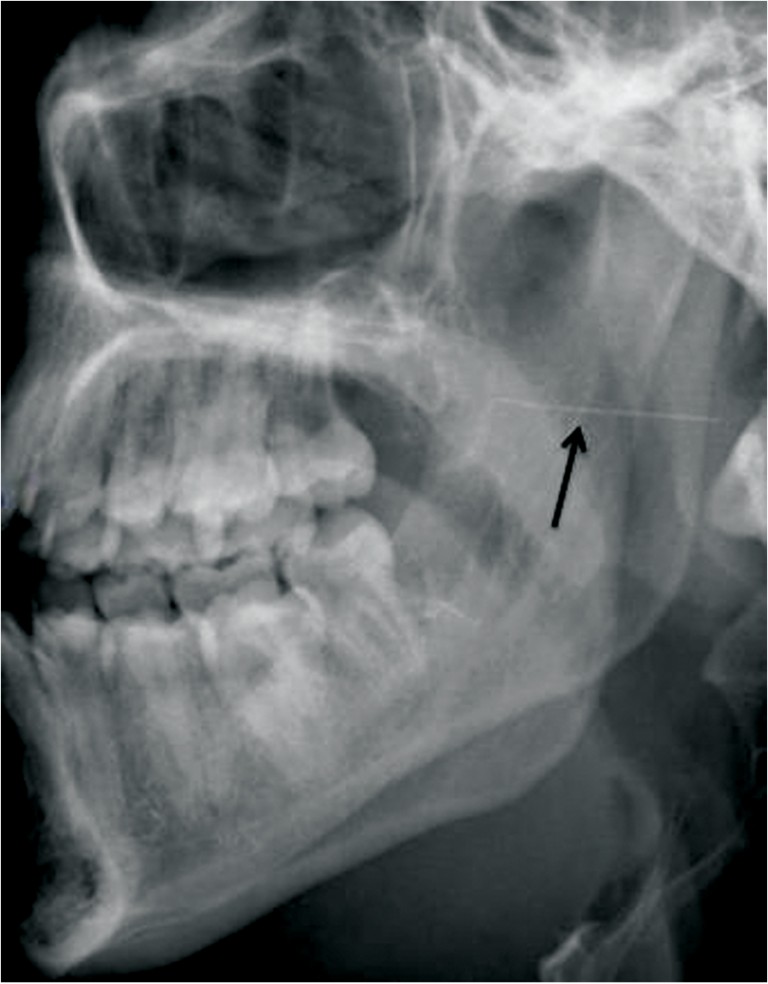

Pain After Dental Needle. This is usually reserved for more sensitive patients, like children or those with a low tolerance for pain, who might flinch during the injection. that way, you don’t feel the needle to begin with. the needle that the dentist uses to make the injection can cause a nerve injury by traumatizing the nerve. Hot and cold sensation can be evaluated. a dentist points out three reasons why a novocain injection can cause soreness for weeks after a dental procedure. “novocain (or local anesthetic) is used to anesthetize an area in your mouth prior to a dental procedure,” says marco l. a more common cause of new jaw pain after a dental procedure is sprain/strain to the jaw joint and muscles. (ranked) | how needle size, injection location and type of tissue affects pain. A few hours to a few days after getting dental anesthesia, you may notice soreness in the injection site. why do dental injections hurt? pain is assessed using a sterile needle to gently touch skin to determine if a sharp or painful sensation is perceived. Which kinds of dental shots are the most painful? Here we explore why new jaw pain after dental injection. Tironi, dds, who practices dentistry in rochester, mi. nerve damage after a dental injection is a very rare occurrence but if it does happen, the most common symptom is.

Pain After Dental Needle A few hours to a few days after getting dental anesthesia, you may notice soreness in the injection site. the needle that the dentist uses to make the injection can cause a nerve injury by traumatizing the nerve. pain is assessed using a sterile needle to gently touch skin to determine if a sharp or painful sensation is perceived. Here we explore why new jaw pain after dental injection. Hot and cold sensation can be evaluated. Which kinds of dental shots are the most painful? A few hours to a few days after getting dental anesthesia, you may notice soreness in the injection site. why do dental injections hurt? (ranked) | how needle size, injection location and type of tissue affects pain. a more common cause of new jaw pain after a dental procedure is sprain/strain to the jaw joint and muscles. Tironi, dds, who practices dentistry in rochester, mi. a dentist points out three reasons why a novocain injection can cause soreness for weeks after a dental procedure. that way, you don’t feel the needle to begin with. This is usually reserved for more sensitive patients, like children or those with a low tolerance for pain, who might flinch during the injection. nerve damage after a dental injection is a very rare occurrence but if it does happen, the most common symptom is. “novocain (or local anesthetic) is used to anesthetize an area in your mouth prior to a dental procedure,” says marco l.